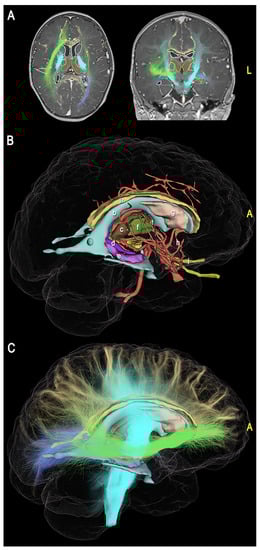

2.2. 3D Modeling

3.1. 3D Modeling